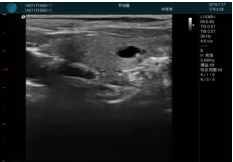

頸動(dòng)脈血流充盈飽滿,無外溢

肝內(nèi)血管顯示清晰,血流敏感無外溢